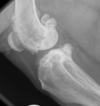

What is the name of the conditon that is shown below?

Cruciate ligament disease